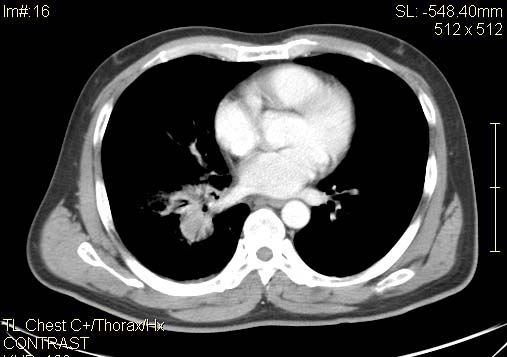

以下是引用qc80012345在2007-4-17 12:33:00的发言:[br]右肺下叶周围型肺癌伴肺门及纵隔内淋巴结转移;比较清楚。

以下是引用qingyuan在2007-4-17 14:19:00的发言:[br]右肺下叶外侧后段胸膜下区节结样病变、分叶、内可见空洞,壁厚薄不均,胸膜凹陷、肺门周围区纹理增粗、僵硬、并近似小结节样改变,肺门区软组织节结、纵膈淋巴结肿大,患者病史长、抗炎治疗无好转炎性改变基本排除,考虑:右肺下叶周围型肺癌伴纵膈及右肺门区淋巴结转移、肺内淋巴管受侵。